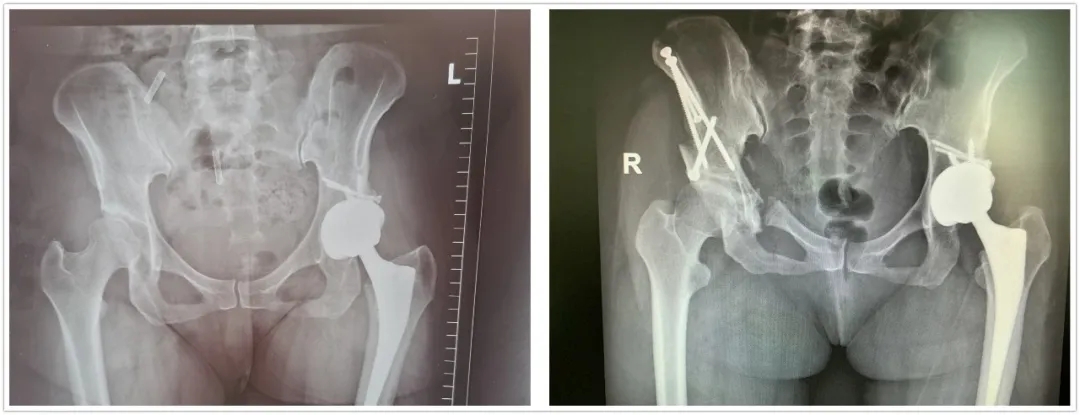

半個(gè)月前,38歲的胡女士(化名)做家務(wù)時(shí),左大腿根出現(xiàn)輕微疼痛,見(jiàn)此情況,胡女士聯(lián)想到了三年前左腿就出現(xiàn)過(guò)這樣的癥狀,因未及時(shí)治療,發(fā)現(xiàn)時(shí)已出現(xiàn)嚴(yán)重的骨關(guān)節(jié)炎,不得不做左側(cè)全髖關(guān)節(jié)置換術(shù)。這次胡女士不敢絲毫耽擱,立即前往北大醫(yī)療淄博醫(yī)院就診。

骨外科主任方俊英接診胡女士后,對(duì)其進(jìn)行詳細(xì)的問(wèn)診和查體,并結(jié)合拍片檢查發(fā)現(xiàn)了右髖已出現(xiàn)輕度的關(guān)節(jié)炎。出于有過(guò)同樣手術(shù)經(jīng)歷的胡女士,深知全髖關(guān)節(jié)置換術(shù)的“后遺癥”。于是胡女士向方主任求助是否有更佳治療方案。方主任得知其顧慮后,立即組織骨外科專家對(duì)胡女士的病情進(jìn)行討論,結(jié)合胡女士的影像資料及癥狀,考慮行髖臼周圍截骨術(shù)是最佳治療方案,既可以緩解癥狀,又可以延緩骨關(guān)節(jié)炎的發(fā)展,延期甚至無(wú)需接受全髖關(guān)節(jié)置換術(shù)。但因其髖臼周圍解剖復(fù)雜、手術(shù)難度大,目前能做此手術(shù)的專家甚少,北大醫(yī)療淄博醫(yī)院合作的山東第一醫(yī)科大學(xué)第一附屬醫(yī)院,骨關(guān)節(jié)外科李樹(shù)鋒主任正是其中一位。于是通過(guò)遠(yuǎn)程會(huì)診系統(tǒng)在線邀請(qǐng)李樹(shù)鋒主任會(huì)診,結(jié)合患者病情,為其制定了詳細(xì)的手術(shù)方案。

經(jīng)過(guò)完善的術(shù)前準(zhǔn)備,手術(shù)如期進(jìn)行。術(shù)中經(jīng)過(guò)多次精確測(cè)量和截骨,在透視下逐一完成髂骨、恥骨支的截骨;在最難實(shí)施的坐骨支截骨階段,李樹(shù)鋒主任、方俊英主任以及骨外科專家團(tuán)隊(duì)克服了坐骨周圍肌肉和深部組織的影響,完成了坐骨—髂骨截骨銜接,并一舉旋轉(zhuǎn)固定成功。手術(shù)經(jīng)歷三個(gè)多小時(shí)順利完成。在醫(yī)護(hù)人員的精心治療下,術(shù)后1周恢復(fù)良好,康復(fù)出院。